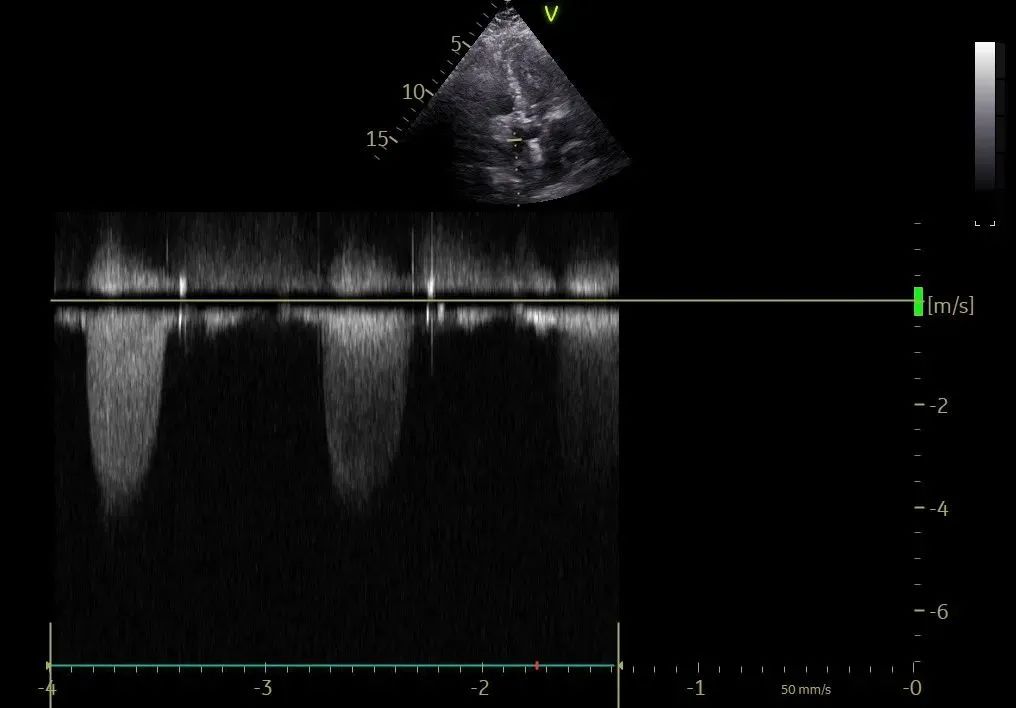

术前超声评估:

主动脉瓣狭窄(重度),收缩期主动脉瓣上流速增快,最大流速约4.5m/s,最大压差约82mmHg,平均流速约3.3m/s,平均压差约49mmHg。左室肥厚,左室舒张功能减低。D-Dimer5.22mg/1FEU,NT-proBNP780.3pg/ml,hsTNI最高270pg/ml,CK-MB最高4.9ng/ml,肌酐56μmol/L,血钾3.7mmol/L。双下肢大动脉超声显示双侧股动脉多发斑块。双侧锁骨下动脉超声未见明显异常。双侧颈动脉超声显示颈动脉内中膜增厚、斑块形成。双下肢深静脉超声显示双下肢深静脉未见血栓。主动脉+腹主动脉+髂动脉CTA:主动脉、髂动脉粥样硬化,主动脉瓣钙化。冠脉造影显示RCA中重度狭窄,于RCA植入支架2枚。